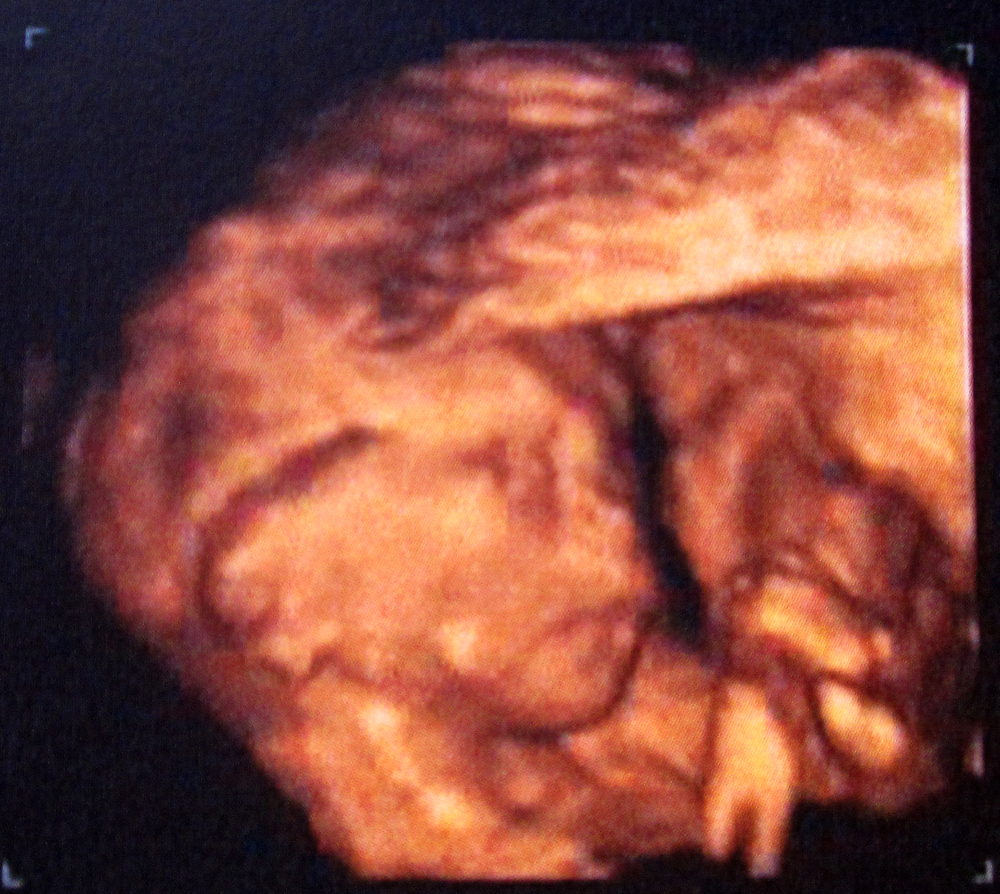

Todo está perfecto, todo esta bien. La tía se lo curra y nos quiere mostrar la carita del peque, que está contra mi bajo vientre y el tío tímido no se quiere mostrar por más que la doctora da pequeños golpes con el cacharro ese untado en gel en mi vientre a ver si se gira. Como siga así me meo encima. Pero nada, no hay forma. Parece que el peque dijera: «anda iros a tomar por culo, dejadme en paz, cagüentó…».

Me hace girarme sobre un lado, lo intenta y nada. Me pide que me gire al otro lado rápido, así lo hago y ¡¡se le ve la carita!! Más bien cara de «Qué ha pasao??!!» del susto que se lleva el pobrecito mío… Es una pasada… Mi chico y yo mirábamos ambas pantallas embelesados y flipados… Aaaains…